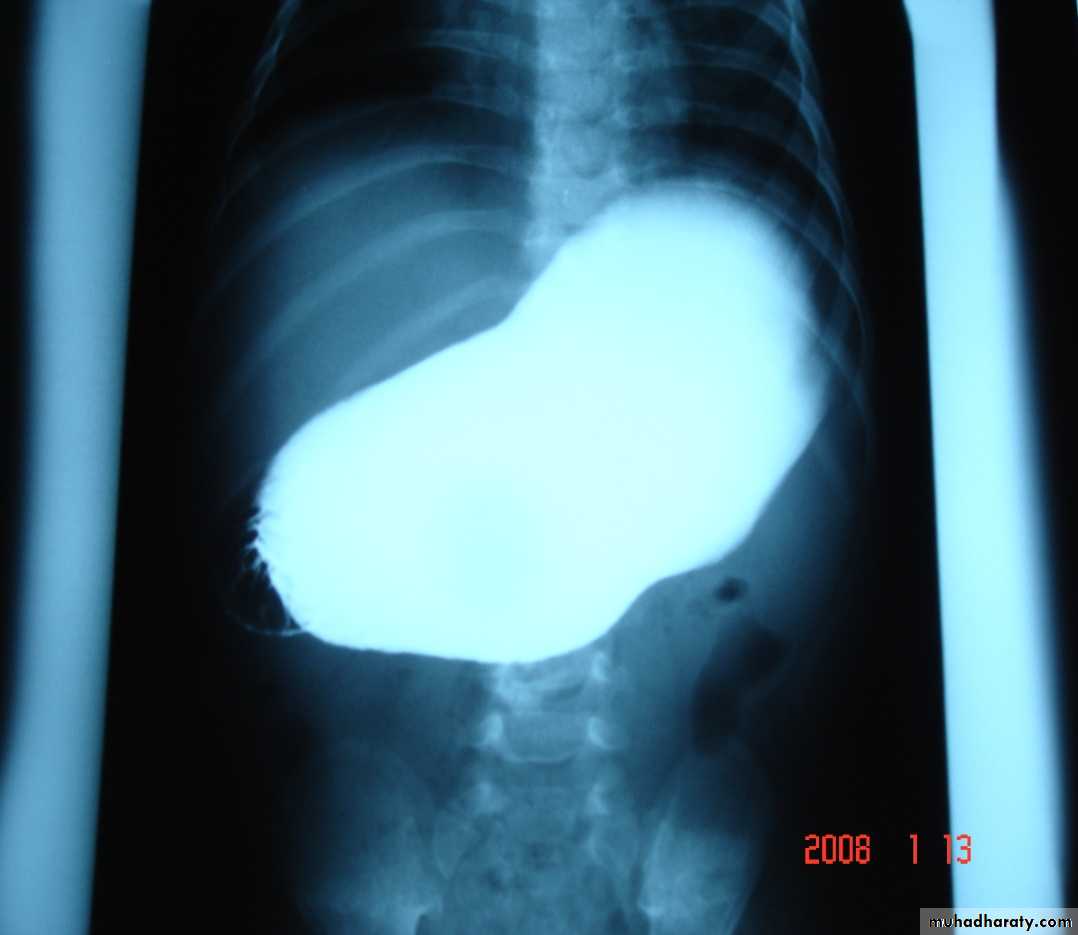

Clinical US Contrast Olive mass studyFeed test